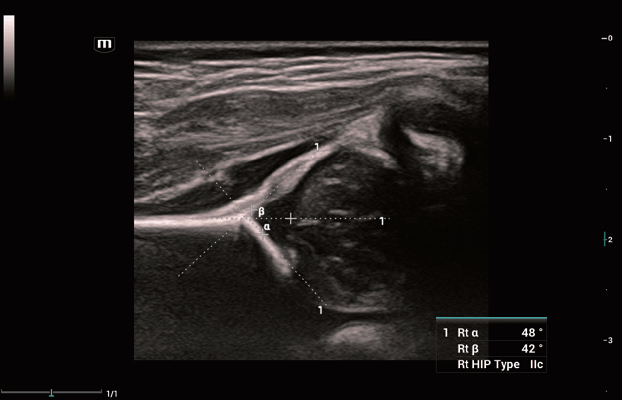

Smart Hip

Inovatívne automatické 2D meranie podľa Grafa

Detekcia kľúčových štruktúr je založená na algoritmoch hĺbokého učenia. Automatické meranie (α a β) a klasifikácia.